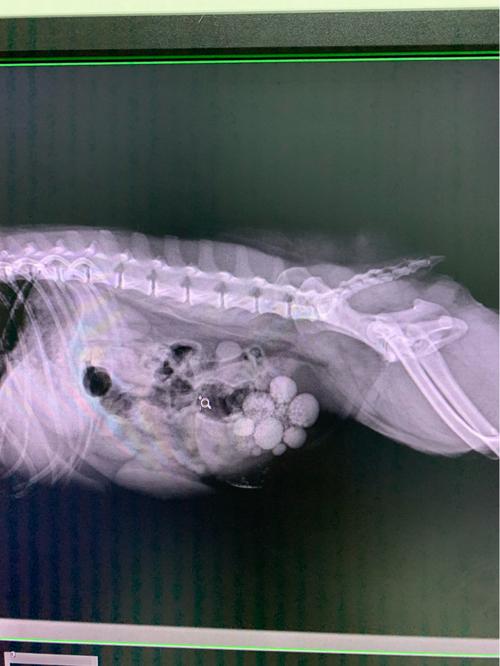

宠物结石主要是由草酸钙、尿酸盐、胆固醇等物质组成,这些物质在体内沉积,形成结石。狗狗得结石的原因有很多,,主要包括遗传因素、饮食因素、环境因素等。下面我们就来看看狗狗结石的症状有哪些。

希望大家能够重视起来,避免狗狗出现不必要的麻烦烦。结石症状一:排尿困难。如果狗狗的尿液颜色比较深,并且有异味,那么就要考虑是不是结石引起的。如果是的话,就要及时带狗狗去医院检查查。

结石症状二:呕吐。如果狗狗出现了食欲不振的情况,并且还伴随着恶心呕吐的症状,那么就要考虑是不是结石引起的。如果是的话,就及时治疗,不然会影响狗狗的健康。结石症状三:尿频。

如果狗狗出现了尿频的情况,那么就要考虑是不是结石引起的。如果是的话,就要及时给狗狗进行治疗,以免结石进一步扩散。结石症状四:呕吐。如果狗狗出现了呕吐的情况,那么就要考虑是不是结石引起的。

如果是结石,那么就会导致狗狗呕吐,并且还会伴随着腹泻的情况。所以,如果发现狗狗出现了这种情况,一定要及时带狗狗去医院进行检查。结石症状:狗狗的尿液中会有石头的存在,并且还会伴随着恶心呕吐的情况。